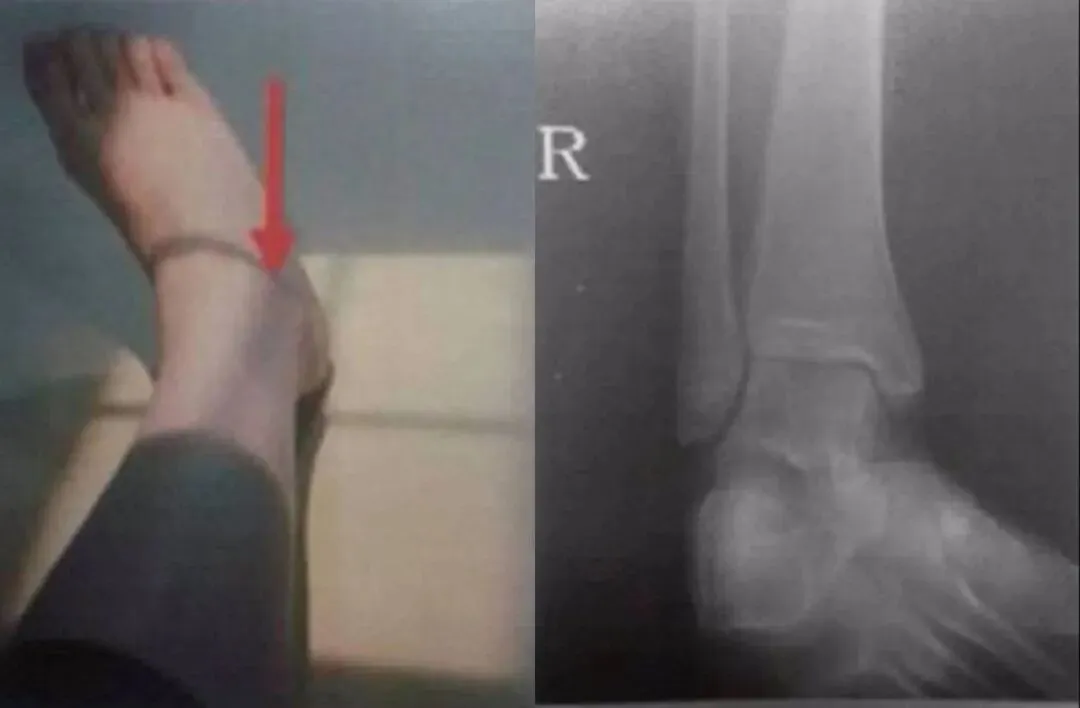

F,62y。跌伤左踝部肿痛活动受限3小时余。

术前CT:

1、左三踝粉碎性骨折,胫距关节半脱位,踝关节软组织肿胀;

2、左足舟状骨、内侧楔骨、第1-4跖骨近端骨折。

术后X线:

1、左三踝骨折内固定术后;

2、考虑左足第3、4跖骨基底部骨折可能;

请结合临床及术前CT。